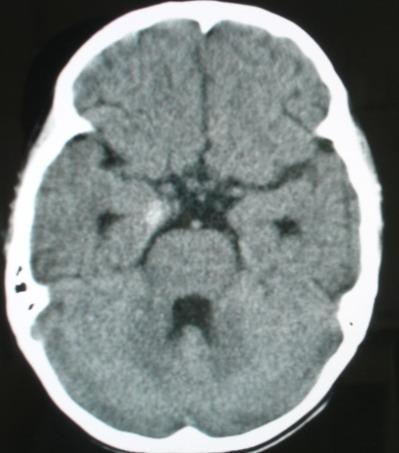

标题: PED0834:M8Y,考虑右侧海绵窦血管瘤

m/8y,右侧眼睑下垂数天,头昏,无呕吐、无外伤史。无搏动性突眼。病人明天来增强。

考虑颈内动脉海绵窦段动脉瘤,建议mri检查。